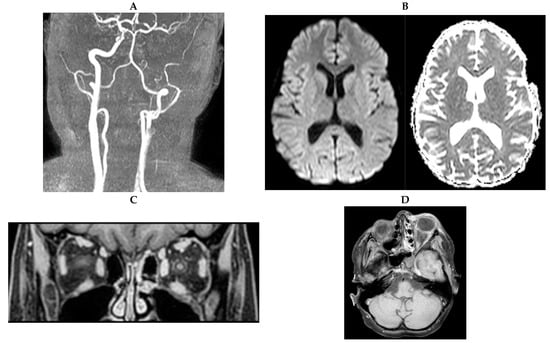

The next morning (day +1), the patient was in coma with dilated pupils unresponsive to light, positive Babinski sign and loss of defensive reflexes. Repeat CT imaging revealed additional complete occlusion of the left proximal anterior cerebral artery (ACA) and partial occlusion of the left middle cerebral artery (MCA) with signs of partial left frontotemporal infarction (Figure 2A–C). In an attempt to rescue as much brain tissue as possible, an interventional thrombectomy of the left ACA and MCA was performed with subsequent stenting of the left ACA and placement of an intracranial Spiegelberg pressure sensor. Postinterventional imaging revealed no evidence of residual perfusion deficits (Figure 2D). In the morning hours of the following day (day +2), autonomous dysregulation was noted. Imaging by transcranial Doppler sonography revealed loss of perfusion of the left ACA and MCA, respectively, and additionally of the right ACA and right posterior cerebral artery (PCA). CT imaging showed a complete infarction of the left hemisphere with a progredient perfusion deficit and beginning brain edema. Subsequent MRI angiography confirmed a nearly complete block of cerebral perfusion, with the only two functional arteries being the right MCA and the right posterior inferior cerebellar artery (PICA) and, at the time, there was suspicion of left intraorbital leukemic infiltration (Figure 3A–C).

Figure 3. Angiography and magnetic resonance (MR) imaging on day +2. (A), TOF-angiography reveals perfusion only via the right internal carotid artery and middle cerebral and proximal parts of the basilar artery (BA). (B), DWI/ADC-Map showing extensive diffusion restriction of the entire left hemisphere and the right basal ganglia. (C), coronar T1w-mDIXON MRI post administration of gadolinum documenting the persistent swelling of the left optic nerve and the left intraorbital eye muscles.